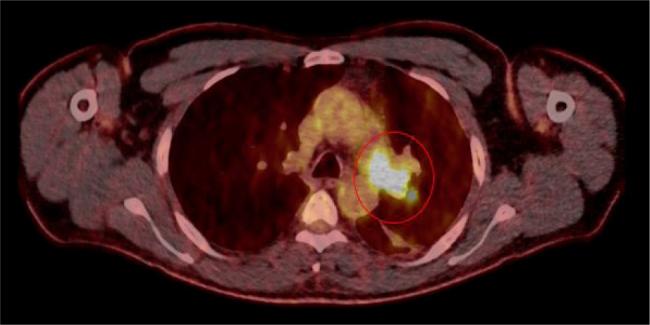

Deep vein thrombosis and pulmonary embolism (PE) are the third most common cardiovascular condition. Pulmonary artery intimal sarcoma (PAIS) is a rare tumour and is often misdiagnosed as a PE. This case report presents a 50-year-old man with fever, dyspnoea, cough and thoracic pain since a month. The patient had a history of two PE episodes. After diagnostic screening for tumour, including laboratory parameters, transthoracic echocardiography, computed tomography scan and positron emission tomography-computed tomography scan, PAIS was diagnosed. Unexplained recurrent PE should raise suspicion of a tumour or PAIS.

Recurrent pulmonary embolism should raise suspicion for tumours.Imaging and histopathology play a crucial role in diagnosis of pulmonary artery intimal sarcoma.Surgical resection as the primary treatment for pulmonary artery intimal sarcoma.